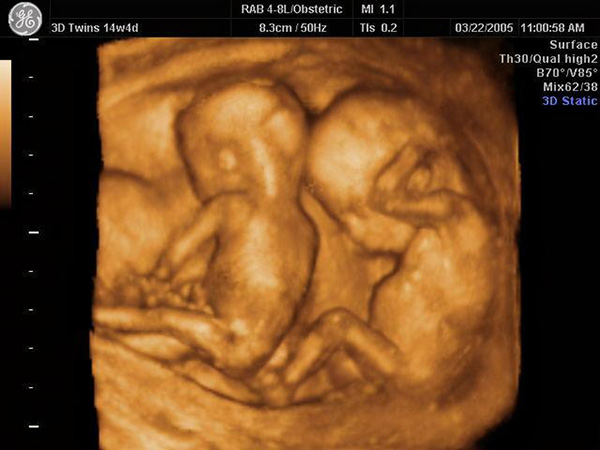

几次产检,彩虹得到的结果都是“孩子很健康”。但她依然不放心,坚持做了对自己来说“天价”的四维彩超,也没有发现孩子发育不正常。对她来说,那段时间,每次产检都像是闯了一道关。

四维彩超(资料图)。彩虹误以为其能帮助自己确认孩子健康,但四维彩超只能直观反映胎儿是否畸形。